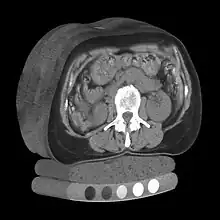

Multiple X-ray computed tomographs (with quantitative mineral density calibration) stacked to form a 3D model

Volume rendering is a set of techniques used to display a 2D projection of a 3D discretely sampled data set, typically a 3D scalar field. A typical 3D data set is a group of 2D slice images acquired, for example, by a CT, MRI, or MicroCT scanner. These are usually acquired in a regular pattern (e.g., one slice every millimeter) and usually have a regular number of image pixels in a regular pattern. This is an example of a regular volumetric grid, with each volume element, or voxel represented by a single value that is obtained by sampling the immediate area surrounding the voxel.